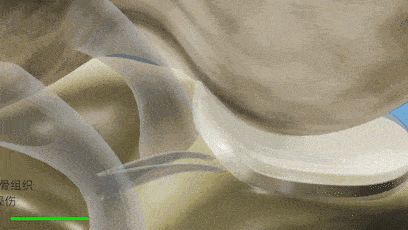

软骨就像一个减震带,关节液就像润滑剂

主要功能就是帮助分担体重对骨面的冲击

软骨磨损会导致疼痛、发炎、肿胀!

一旦关节液消耗完,身体只要动

膝关节之间的这层软骨每一天都在发生磨损

氨糖能够修复受损软骨,补充软骨营养、促进关节液生成

而硫酸软骨素则能促进软骨再生。

氨糖为软骨补充营养,修复磨损的关节软骨;

硫酸软骨素合成软骨滑液,润滑软骨,减缓软骨耗损。